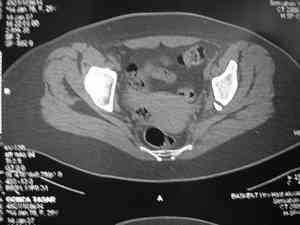

прилагаю пример с такой же давностью травмы, репонировали аппаратом

> в аппарате или одномоментно открыто. Лично я склоняюсь к аппаратному лечению на первом этапе.